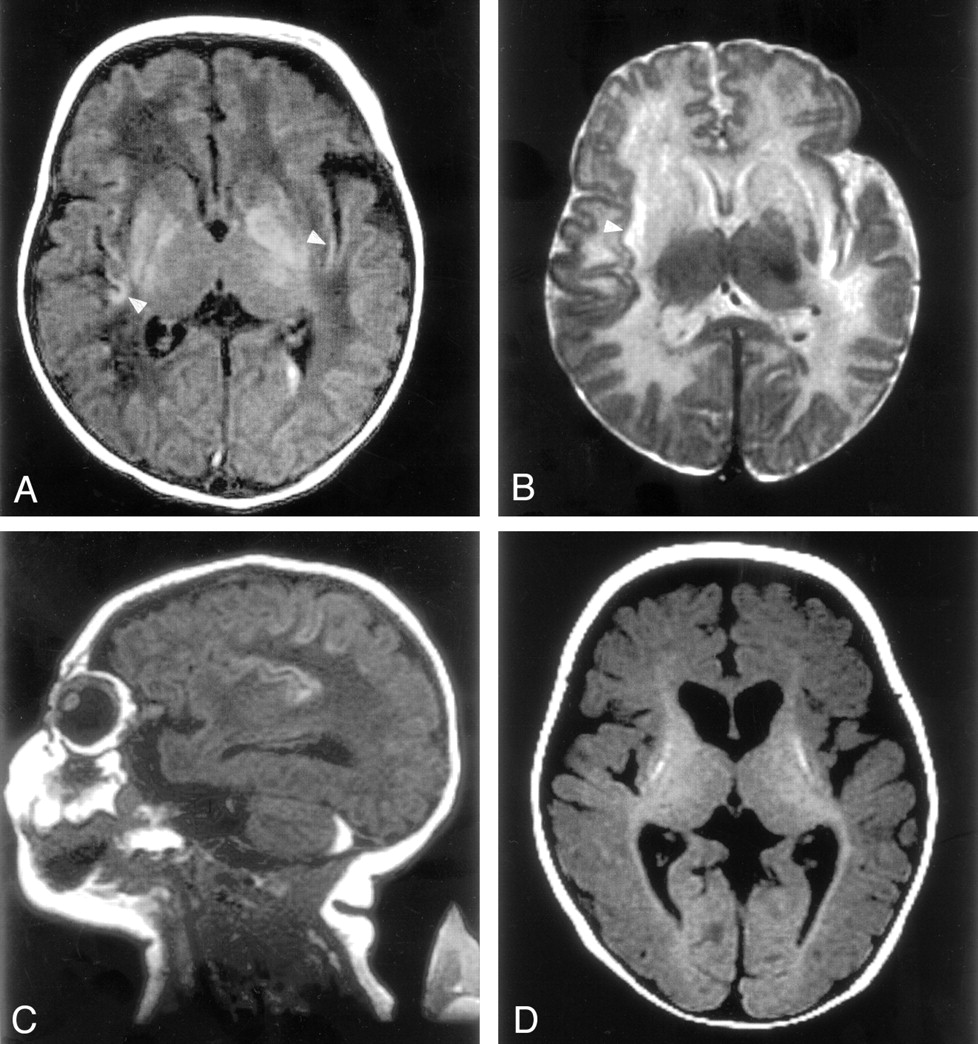

MR images in case 1.

A, T1-weighted image (500/16/2) of the brain demonstrates T1 shortening in the bilateral lentiform nuclei (globi pallidi more than the putamina) and insular cortex (arrowheads). Left intraventricular hemorrhage is recognized.

B, T2-weighted image (3000/120/1) shows low signal intensity in the left globus pallidus and high signal intensity in the corpora striata and white matter subjacent to the insular cortex (arrowhead).

C, Sagittal T1-weighted image shows T1 shortening in the deep sulci of the insular and perirolandic regions and a retrocerebellar subdural hematoma.

D, T1-weighted image obtained at the age of 7 months shows volume loss in the basal ganglia with T1 shortening in the putamina, reduced volume of cerebral white matter, and diffuse cortical atrophy. Myelination was recognized in the posterior limb of the internal capsule and in the optic radiation.

This girl, aged 20 months at the time of this report, was the third child born to healthy young nonconsanguineous parents, and the older sister of the patient in case 2. The patient had no known history of in utero exposure to infections, drugs, or other teratogens. She was vaginally delivered at term without complications. She presented at the age of 2 days with lethargy, anorexia, and respiratory distress, progressing to coma, generalized tonic-clonic seizures, and the need for ventilatory support. Elevated serum ammonia levels as high as 1700 μmol/L (normal range, 64–107 μmol/L) were found. Electrolyte levels and liver function results were normal, with negative blood and CSF cultures. Quantitative serum amino acid analysis revealed the following values: glutamate, 362 μmol/L (normal range, 0–50 μmol/L); glutamine, 1268 μmol/L (normal range, 538–958 μmol/L); citrulline, 0 μmol/L (normal range, 8–29 μmol/L); arginine, 26 μmol/L (normal range, 22–88 μmol/L); and ornithine, 47 μmol/L (normal range, 49–151 μmol/L). Argininosuccinate was undetectable, and urinary orotate was 1–2 μmol/mol Cr (normal range, 0–5 μmol/mol Cr). Urine organic acid analysis revealed no specific abnormalities. DNA analysis showed no mutation in the OTC gene. A diagnosis of deficiency of CPS I reaction step was suspected. After 40 hours of hemodialysis and medical therapy (intravenous sodium benzoate, sodium phenylacetate, and arginine hydrochloride), the patient’s serum ammonia level normalized to 50 μmol/L. At the age of 2 weeks, an MR study was performed with a 1.5-T superconducting magnet (GE Medical Systems, Milwaukee, WI). Spin-echo T1-weighted images (TR/TE/NEX, 500/16/2) of her brain demonstrated T1 shortening in bilateral lentiform nuclei (globi pallidi more than putamina) and the deep sulci of insular and perirolandic regions (Fig 1A and C). Spin-echo T2-weighted images (3000/120/1) showed bilateral low signal intensity in the globi pallidi and high signal intensity in the corpora striata and white matter subjacent to the insular and perirolandic cortices (Fig 1B). Intraventricular hemorrhage and retrocerebellar subdural hematoma were also identified. At age 7 months, after two subsequent episodes of significant hyperammonemia, the patient’s brain MR images showed volume loss, most notably in the basal ganglia. In addition, the images depicted T1 shortening in the putamen and diffuse cortical atrophy (Fig 1D). T2-weighted images showed T2 prolongation in the lentiform nuclei. Myelination was slightly delayed for her age. The patient underwent cadaveric liver transplantation at the age of 8 months. Since the transplantation, she has been asymptomatic but has truncal hypotonia, appendicular hypertonia, choreoathetosis, and global neurodevelopmental delays. This aggregate clinical picture was consistent with the neuroimaging findings.